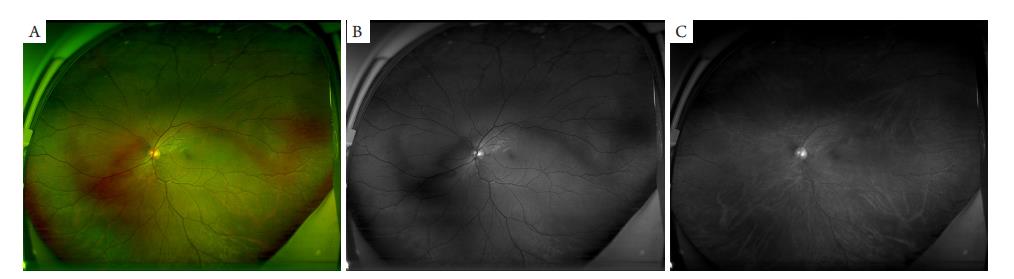

随着该项技术的不断改良,Friberg等[19]在此前报道的扫描激光检眼镜[22]基础上设计了一种通过大型椭圆镜增加眼底成像范围至200 °的免散瞳非接触式扫描激光检眼镜(ultra-wide-field scanning laser ophthalmoscopy,UWF SLO),标志着WFFI发展至UWFFI,其中以UWF SLO与超广角眼底荧光素血管造影(ultra-wide-field fundus fluorescein angiography,UWFFA)为主要代表,目前前者应用更为广泛,其配备有双焦点凹面椭圆镜与共焦扫描激光检眼镜,利用椭圆镜点对点反射激光原理并通过眼内中心视角测量方式实现小瞳下采集水平200°、垂直170°的超大眼底视野范围[10,23],采集单张正位(后极部)眼底图像即可清晰成像至锯齿缘(图3A),配合其鼻颞侧眼位引导甚至可以达到水平220 °~240 °的眼底范围[24]。此外,UWF SLO利用红绿双色激光成像原理实现视网膜的彩色图像,克服以往采集图像颜色单一的不足,而不同颜色的激光波长不同,其所观察到眼底结构也各有差异,绿色激光(532 nm)图像主要显示前视网膜结构及其血管,而红色激光(633 nm)图像则突出显示脉络膜结构及其血管(图3 B,3C);同时,该设备还配备有蓝色激光(488 nm),可用于UWFFA[10]。即便如此,早期UWF SLO图像周边存在显著的非线性扭曲,这与三维球立体面转换为二维平面图像的数字化投影无法得到完全精准实现密切相关[25]。由于椭球镜非对称光学特性[23]与眼睑、睫毛伪影[26]等因素影响,导致上、下方成像及对比度更为受限;并且其严重的红绿伪色仍是该设备目前有待解决的主要问题之一[27-28]。而作为另一主流UWFFI的UWFFA在成像方面则优于UWF SLO,虽然其采集视网膜范围仅有102 °(图4 ),但它可提供更好的上、下方视网膜可视区、更少的眼睑睫毛伪影和更均匀的对比度[29-30],因为目前UWFFA就上述问题配备了相应程序,可使图像失真被自动校正并增强上、下方可视化对比度,同时利用其相关程序将平面图像转换成立体投影图像,以此测量更为精确的眼底长度及面积[9,31]

图3 正常成年人左眼UWF SLO

Figure 3 Fundus color images of the left eye of a normal adult using UWF SLO

(A)200°超广角彩色眼底图像;(B)绿色激光超广角图像;(C)红色激光超广角眼底图像。

(A) 200° UWF SLO fundus color image; (B) UWF SLO fundus image using the green laser; (C) UWF SLO fundus image using the red laser.